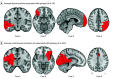

Results: Lesion locations from 76 patients with poststroke epilepsy (39 [51%] male; mean [SD] age, 61.0 [14.6] years; mean [SD] follow-up, 6.7 [2.0] years) and 625 control patients with stroke (366 [59%] male; mean [SD] age, 62.0 [14.1] years; follow-up range, 3-12 months) were included in the discovery data set. Lesions associated with epilepsy occurred in multiple heterogenous locations spanning different lobes and vascular territories. However, these same lesion locations were part of a specific brain network defined by functional connectivity to the basal ganglia and cerebellum. Findings were validated in 4 independent cohorts including 772 patients with brain lesions (271 [35%] with epilepsy; 515 [67%] male; median [IQR] age, 60 [50-70] years; follow-up range, 3-35 years). Lesion connectivity to this brain network was associated with increased risk of epilepsy after stroke (odds ratio [OR], 2.82; 95% CI, 2.02-4.10; P < .001) and across different lesion types (OR, 2.85; 95% CI, 2.23-3.69; P < .001). Deep brain stimulation site connectivity to this same network was associated with improved seizure control (r, 0.63; P < .001) in 30 patients with drug-resistant epilepsy (21 [70%] male; median [IQR] age, 39 [32-46] years; median [IQR] follow-up, 24 [16-30] months).

Conclusions and relevance: The findings in this study indicate that lesion-related epilepsy mapped to a human brain network, which could help identify patients at risk of epilepsy after a brain lesion and guide brain stimulation therapies.